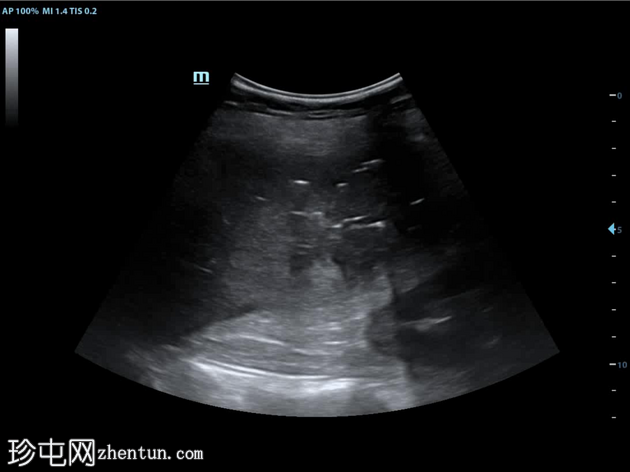

12小时后

超声

纵切面(肝脏

第6和第7段)

9.jpg

将穿刺针插入第6段肝脓肿。抽取血脓性液体。

插入导丝,扩张通道,然后插入猪尾导管。猪尾导管用引流锁固定。导管尖端位于肝脓肿内。

对肝包膜下积液重复相同操作(未显示)。